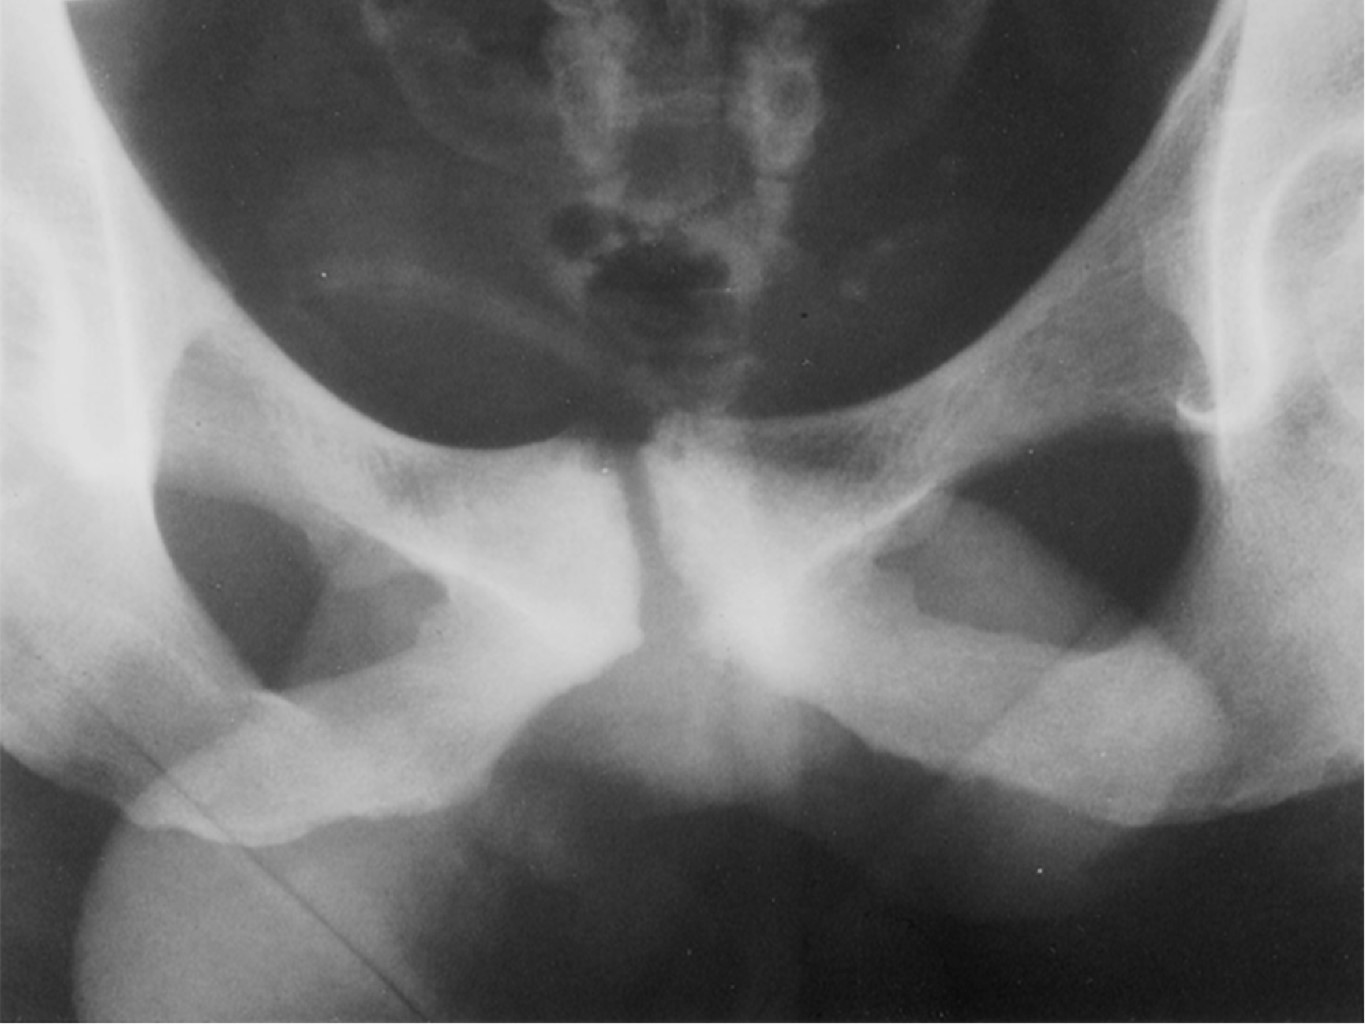

Podemos realizar una primera aproximación diagnóstica solicitando una radiografía de pelvis, con proyecciones anteroposteriores y axiales, por su facilidad y coste a la hora de realizarse. Comúnmente, evidenciaremos esclerosis subcondral, irregularidad de la sínfisis y resorción ósea, en casos avanzados (Figura 1).8 La prueba que mayor información nos va a aportar será la resonancia magnética (RM). Será frecuente encontrarse un edema medular difuso, el cual se extiende desde la superficie subcondral, que a menudo involucra ambas ramas púbicas.9 Además, se suelen encontrar signos de periostitis, irregularidades de las superficiales articulares, erosiones, osteofitos anteriores y posteriores y quistes subcondrales. El signo de la herradura está comúnmente presente (Figura 2). Las uniones miotendinosas se conservan, a menos que haya tendinopatía coexistente.9

Se seleccionaron dos pacientes de 65 y 72 años. Ambas presentaron dolor en la sínfisis que les limitaba las actividades de la vida diaria. Una de ellas realizaba actividad física moderada que había tenido que cesar por completo debido a las molestias continuas. Se realizaron estudios de imagen que comenzaron con radiografías simples de pelvis (Figura 3).